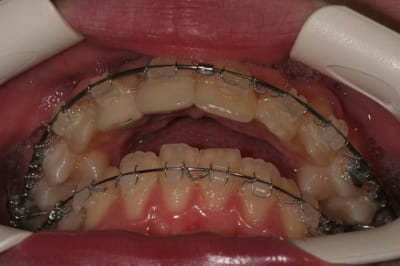

résultat d’élastiques de Cl.II.,

(à ce propos, les arc d’ORMCO, sont très bien et pas cher)

@+ Bjc.